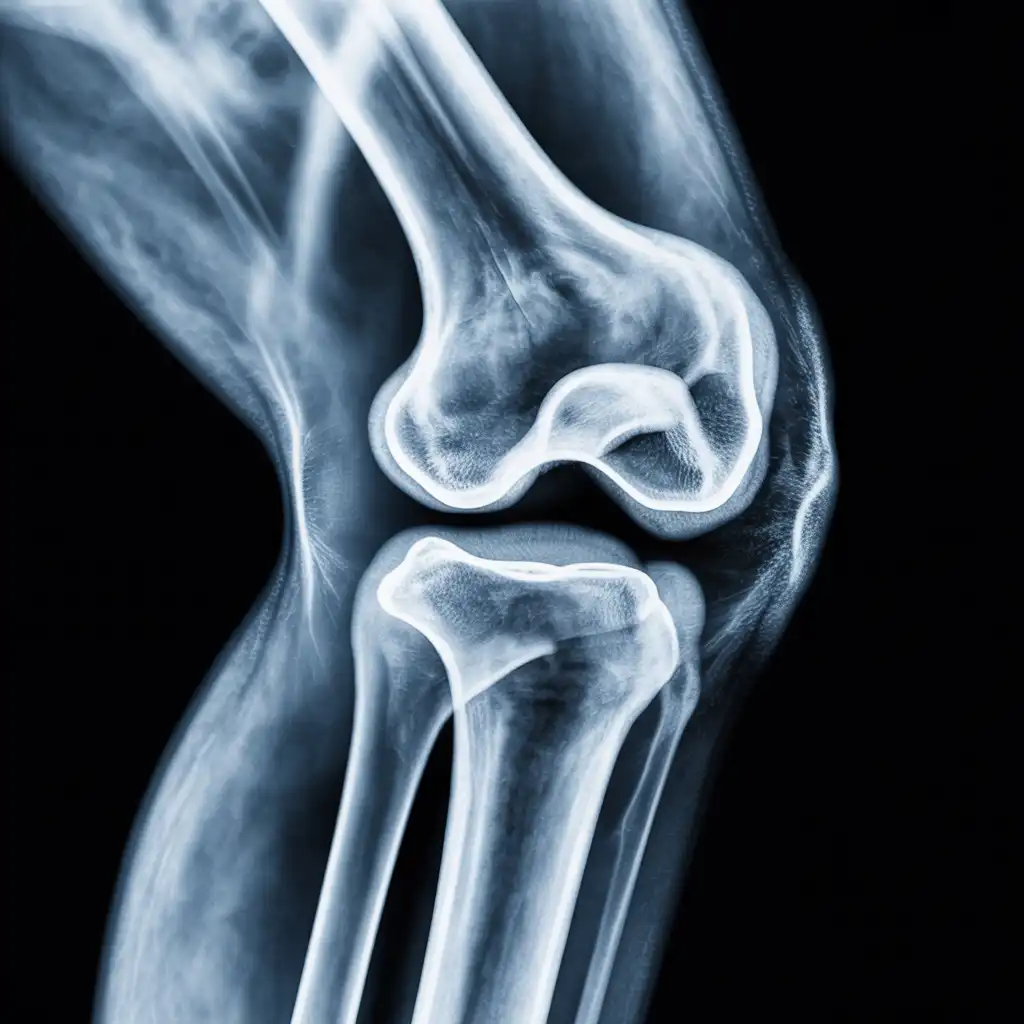

Da anni offriamo un servizio di radiografie a domicilio pensato per garantire ai nostri pazienti la stessa qualità diagnostica degli esami eseguiti in ospedale, ma con la comodità e la sicurezza della propria casa.

Abbiamo effettuato migliaia di esami direttamente presso abitazioni, residenze e strutture assistenziali, utilizzando apparecchiature digitali portatili certificate e procedure rapide e sicure.